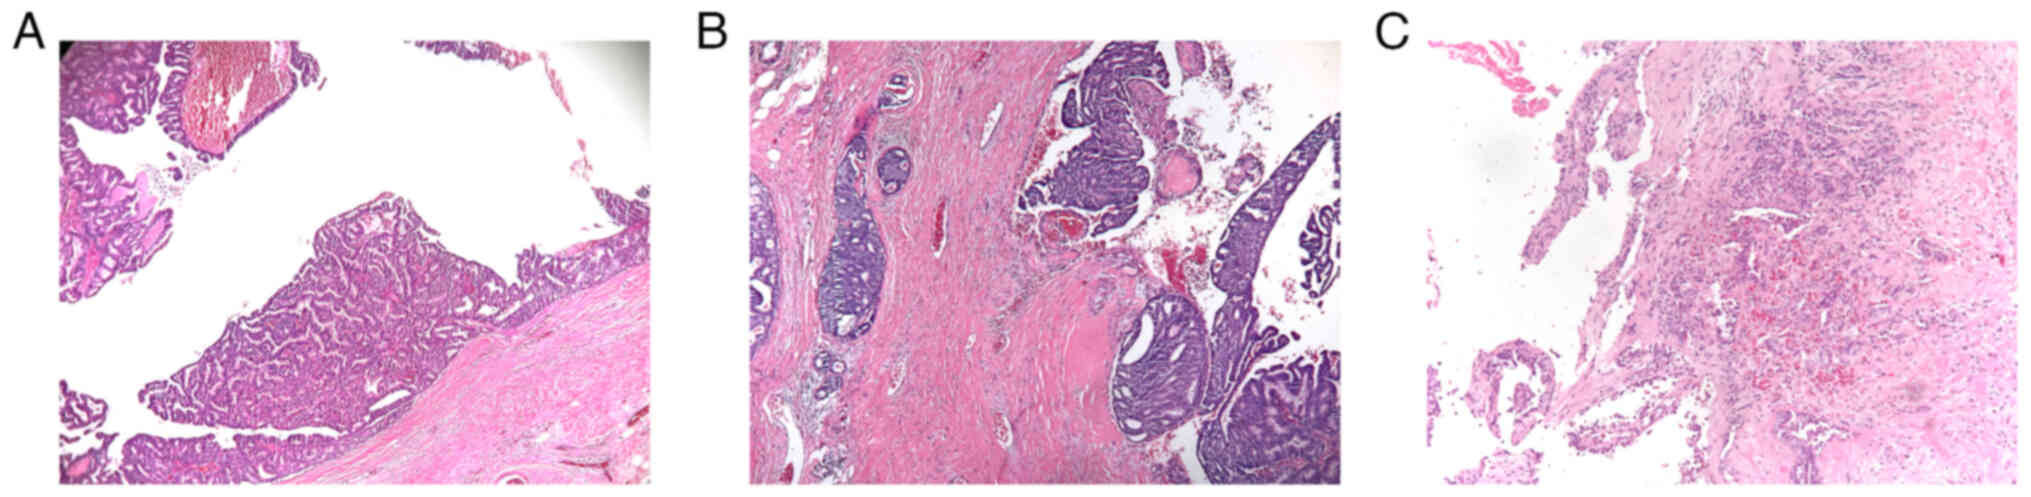

Histopathological examination of EPC showed a well-defined lesion of papillary carcinoma within a dilated duct comprised of fibrovascular cores covered by single or multiple layers of neoplastic cells, surrounded by a fibrous capsule. The surrounding fibrous capsule was thick and may have been accompanied by inflammatory cell infiltration (Fig. 1). According to the Nottingham Grading System in primary breast cancer, 5 EPC cases were high nuclear grade (10.6%), and they were all EPC associated with invasive carcinoma. Subsequent immunohistochemical analyses demonstrated that the EPC cases were primarily estrogen receptor (ER)- and progesterone receptor (PR)-positive (ER, 91.5%; PR, 80.9%). Notably, all 4 ER-negative cases were diagnosed with EPC associated with invasive carcinoma. As for the 9 PR-negative cases, 2 were pure EPC, 2 were EPC associated with DCIS and 5 were EPC associated with invasive carcinoma. According to the American Society of Clinical Oncology-College of American Pathologists Guideline for HER2 testing in breast cancer (17), cancer with HER2 overexpression refers to those patients who are HER2 IHC (3+), or HER2 IHC (2+) and FISH (+). Therefore, the majority of lesions were HER2-negative breast cancer (97.9%) in the present study, except for only one HER2 (2+) patient who had invasive EPC and was positive in the subsequent FISH analysis (Table II). Myoepithelial markers, such as p63, α smooth muscle antigen (α-SMA) and cytokeratin (CK)5/6, were negative in the majority of lesions (p63, 85.1% negative; α-SMA, 76.6% negative; CK5/6, 87.2% negative), which indicated that myoepithelial cells were often absent both in the fibrovascular cores and at the periphery of the tumor nodules of EPC (Fig. 2). A summary of the immunohistochemical analysis of the cohort is shown in Table II.

Figure 1.

Subtypes of EPC of the breast. (A) Pure EPC: A well-defined classic papillary carcinoma surrounded by a thick fibrous capsule. (B) EPC associated with DCIS: Around the EPC, multiple cribriform DCIS of intermediate nuclear grade were observed. (C) EPC associated with invasive carcinoma: Invasive carcinoma was observed beyond the fibrous capsule of the EPC by haphazardly arranged, irregular-shaped, tumor nests. Magnification, ×100. All the EPC cases were observed using H&E staining. EPC, encapsulated papillary carcinoma; DCIS, ductal carcinoma in situ.